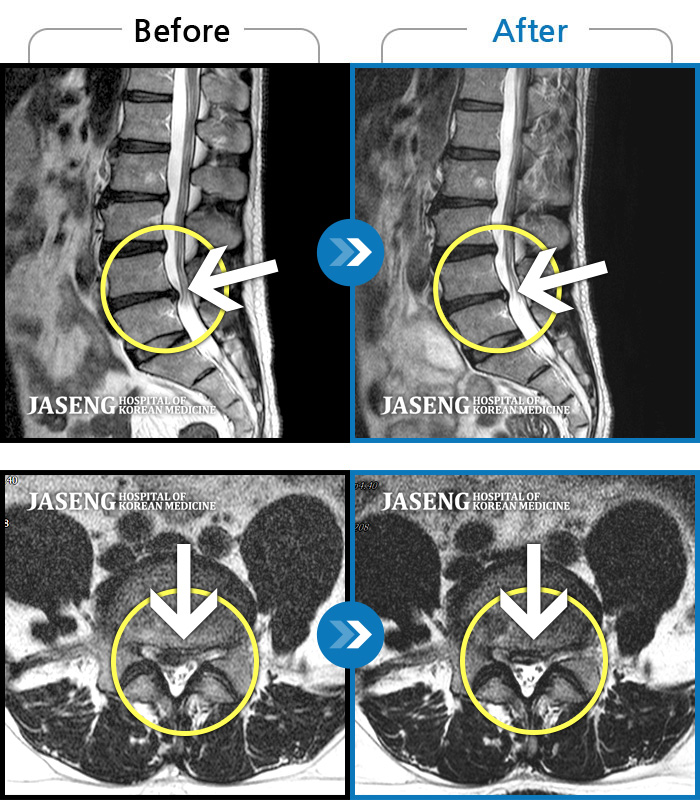

허리디스크

인천 · 강아현 원장

물건을 들다 삐끗한 후 발생한 허리 통증 및 하지 방사통, 하지 감각 저하 및 근력 저하 발생

촬영시기

2025.03.04 ~ 2025.09.10

2025.09.22